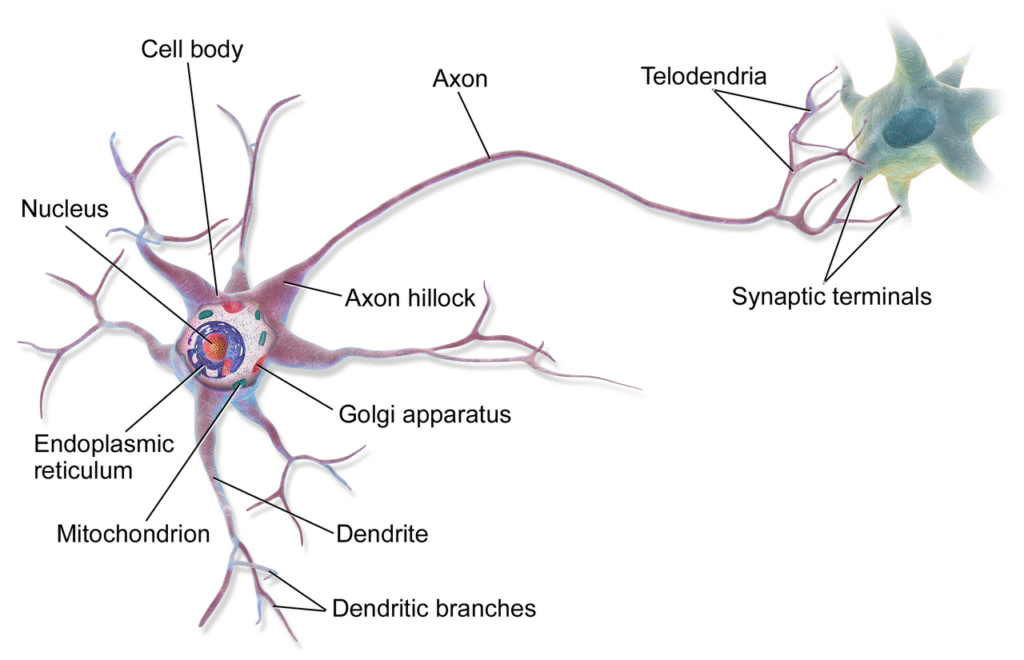

Khi được sử dụng cho mục đích điều trị, steroid thường được pha trộn với thuốc tê hoặc sử dụng đơn độc trong các mũi tiêm phong bế rễ thần kinh chọn lọc. Steroid trong phong bế thần kinh hoạt động thông qua sự kết hợp của các cơ chế sau:

- Ức chế hoạt động của một số enzyme: Chẳng hạn như phospholipase A – tác nhân gây kích ứng thần kinh và đau.

- Phong bế các sợi dẫn truyền cụ thể (sợi C): Các sợi C nằm trong dây thần kinh bị ức chế dẫn đến việc giảm truyền tín hiệu đau về não.

- Giảm tính thấm của các sợi thần kinh đối với nguồn cung cấp máu: Từ đó làm giảm khả năng dẫn truyền cảm giác đau.

Thông qua các cơ chế này, các tín hiệu đau được truyền đi bởi dây thần kinh mục tiêu có thể được thuyên giảm đáng kể.